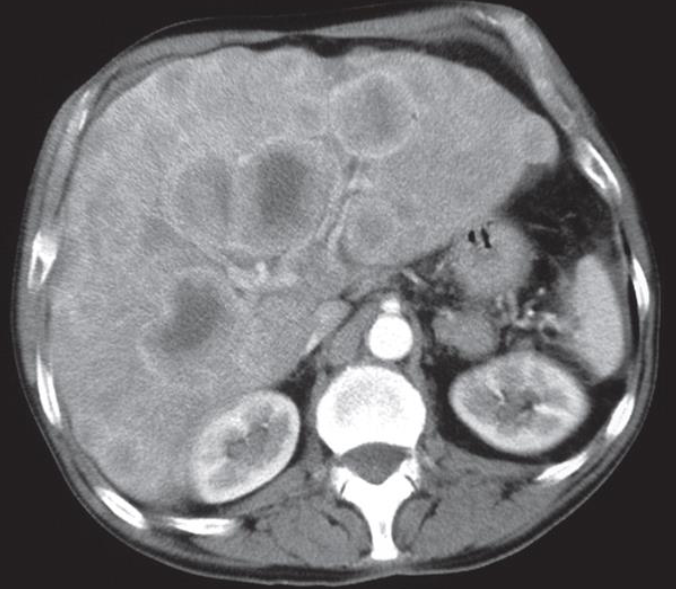

The patient had carcinoma of the bronchus.

CT scan of liver metastases. There are a large number of low density lesions in both lobes of the liver, which show enhancement around their edges.

LIVER METASTASIS

Imaging examination CT scan